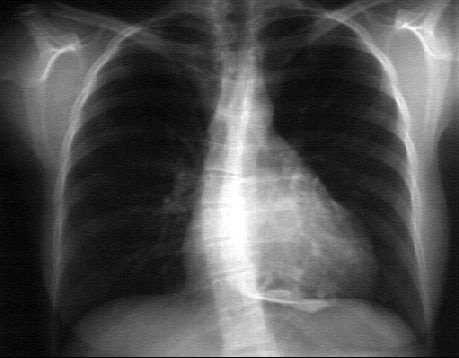

PA and Lateral

Click on the X rays to enlarge them.

Choose the best interpretation of the chest X rays:

Pericardial effusion

Normal

Lung mass and pericardial effusion

Pericardial calcification

Pericardial cyst